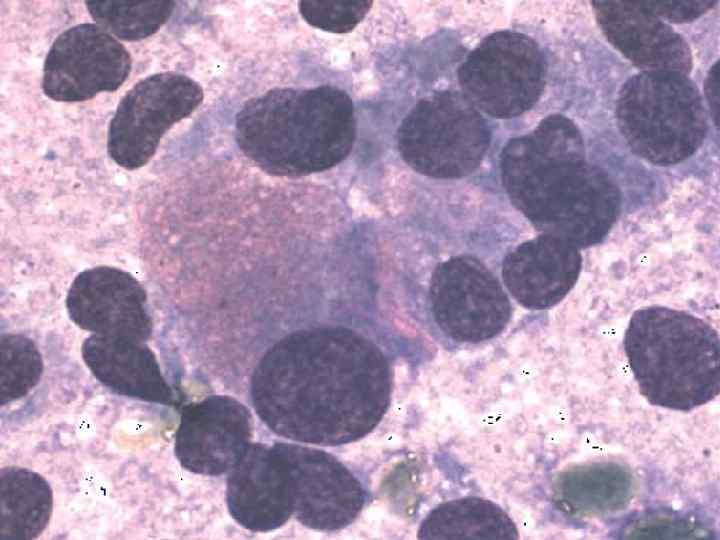

Фотографии опухоли медуллярной аденокарциномы